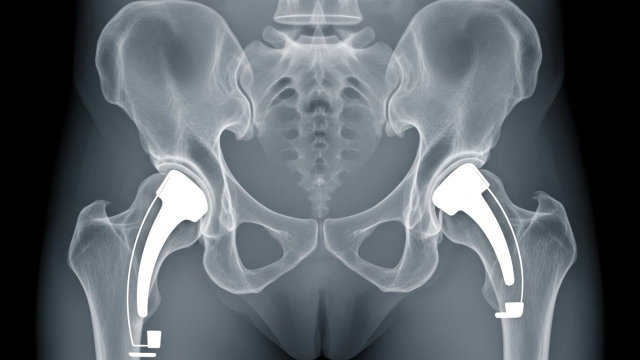

2) 무릎 vs 고관절, 비용 차이 포인트

같은 “인공관절”이라도 부위와 수술 난이도, 입원/재활 패턴이 달라서 총비용이 달라집니다. 특히 고관절은 골절/괴사 등 상황에 따라 입원·재활이 달라질 수 있어요.

상세 3) 무릎·고관절별로 비용이 달라지는 이유

무릎은 보행·계단·앉았다 일어날 때 통증이 심해 수술을 고민하는 경우가 많고, 고관절은 통증 위치가 사타구니/엉덩이 쪽으로 나타나 “허리 문제”로 착각하기도 합니다. 부위마다 수술 접근 방식과 회복 루틴이 달라져 비용 구조도 달라질 수 있어요.

• 무릎: 수술 후 초기 보행·근력 회복 중심 재활이 중요

• 고관절: 자세·보행 교정 + 낙상 위험 관리가 함께 중요